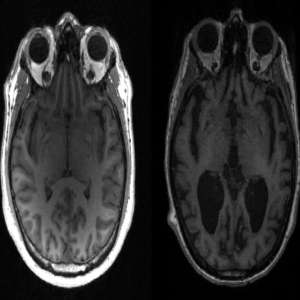

علماء يكشفون عن سبب جيني محتمل للإصابة بمرض ألزهايمر